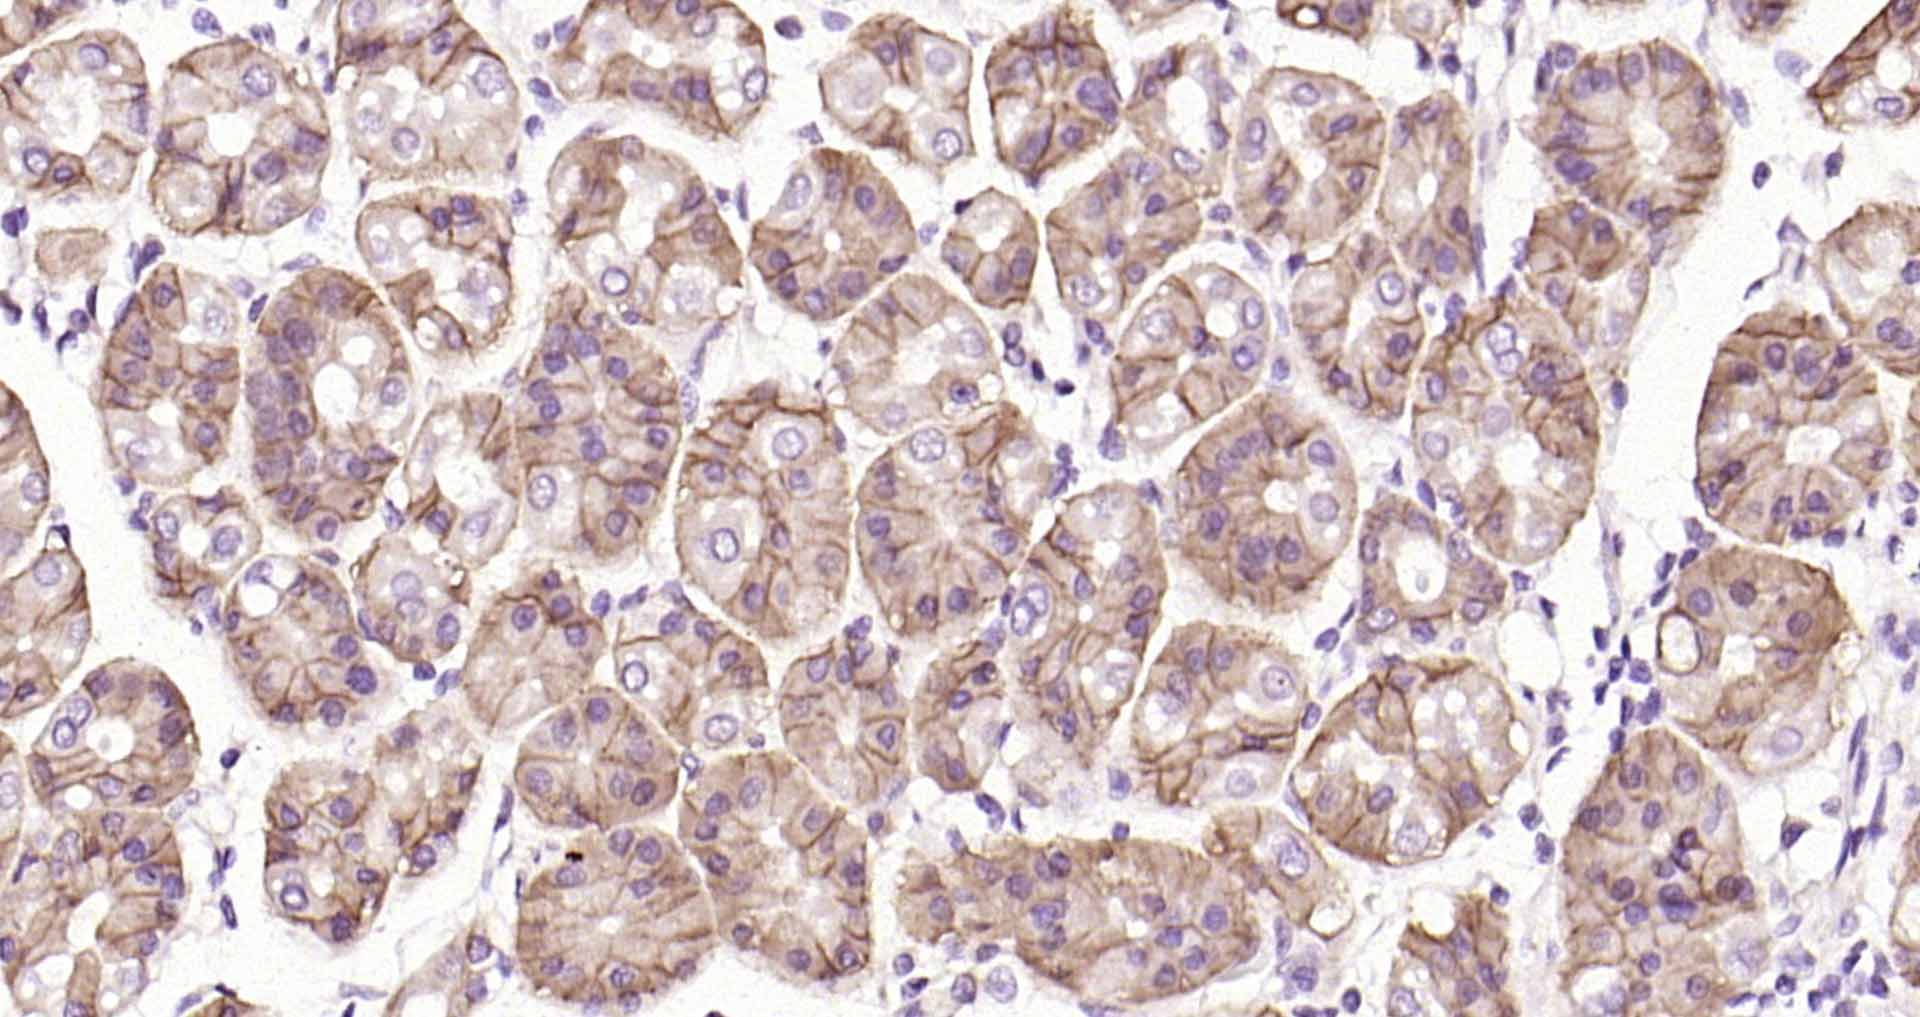

Paraformaldehyde-fixed, paraffin embedded Human fundus of stomach; Antigen retrieval by boiling in sodium citrate buffer (pH6.0) for 15 min; The section was incubated with Claudin 18 Monoclonal Antibody, Unconjugated (bsm-34122M) at 1:200 overnight at 4°C, followed by conjugation to the bs-40296G-HRP and DAB (C-0010) staining.

Paraformaldehyde-fixed, paraffin embedded Human Stomach; Antigen retrieval by boiling in sodium citrate buffer (pH6.0) for 15 min; The section was incubated with Claudin 18 Monoclonal Antibody, Unconjugated (bsm-34122M) at 1:200 overnight at 4°C, followed by conjugation to the bs-40296G-HRP and DAB (C-0010) staining.